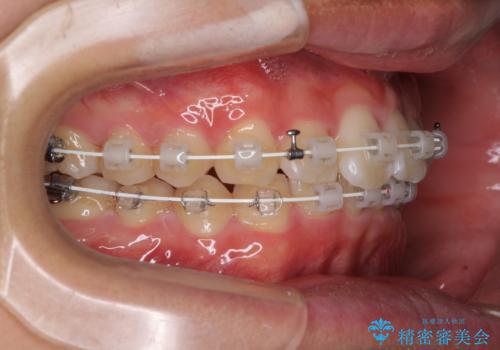

- 審美装置

- 治療期間

- 11ヶ月

インビザラインでの治療も可能でしたが、深い咬み合わせと奥歯の咬み合わせを改善するにあたり、ワイヤー矯正の方が治療期間を短縮できると判断し、ワイヤー矯正をお勧めしました。

結果として、1年かからずに奥歯の咬み合わせを改善することができました。